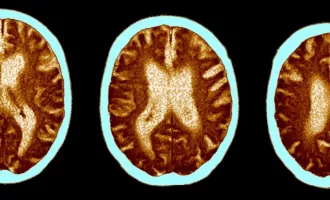

سلامت مطالعه جدید: کرونا خطر ابتلا به آلزایمر، پارکینسون و سکته مغزی را افزایش میدهد

تحقیقات جدید کنگره آکادمی نورولوژی اروپا در وین از افزایش خطر ابتلا به چندین اختلال عصبی در بیماران، پس از ابتلا به کرونا خبر میدهد. ...

علمی ابتلا به کرونای حاد معادل ۲۰ سال مغز را پیر میکند

محققان دانشگاه کمبریج میگویند ابتلا به کرونای حاد میتواند روی تواناییهای شناختی و مغز افراد تاثیرگذار باشد تا جایی که اثر این بیماری معادل بیست ...